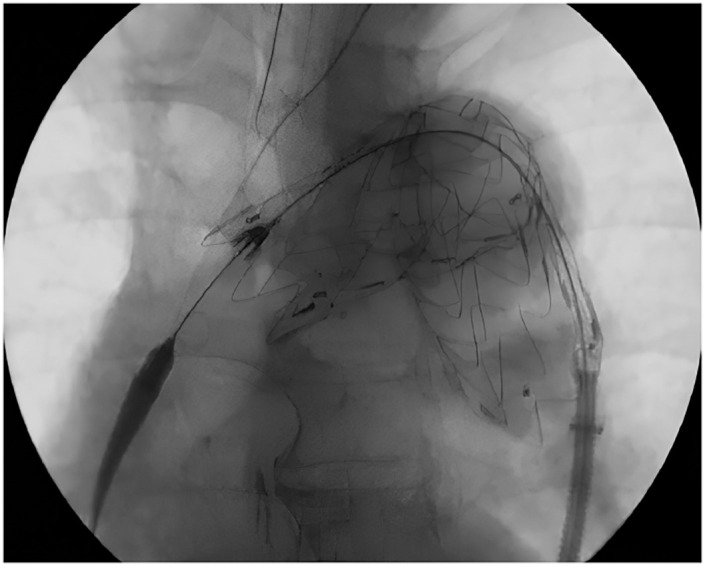

Early Tip Capture Release and Push-Up Technique Using the Valiant Stent Graft System for Aortic Arch Aneurysms.

During thoracic endovascular aneurysm repair for aortic arch aneurysms, deployment of the stent graft parallel to the aortic neck is crucial to preventing a type Ia endoleak from the proximal end. We report the early tip capture release and push-up technique that comprises early release of the proximal bare stent, which is typically deployed last during stent graft deployment, followed by a push-up maneuver after landing the proximal edge, thus allowing conformation to the aortic morphology. This technique is effective even for complex aortic arch anatomy.